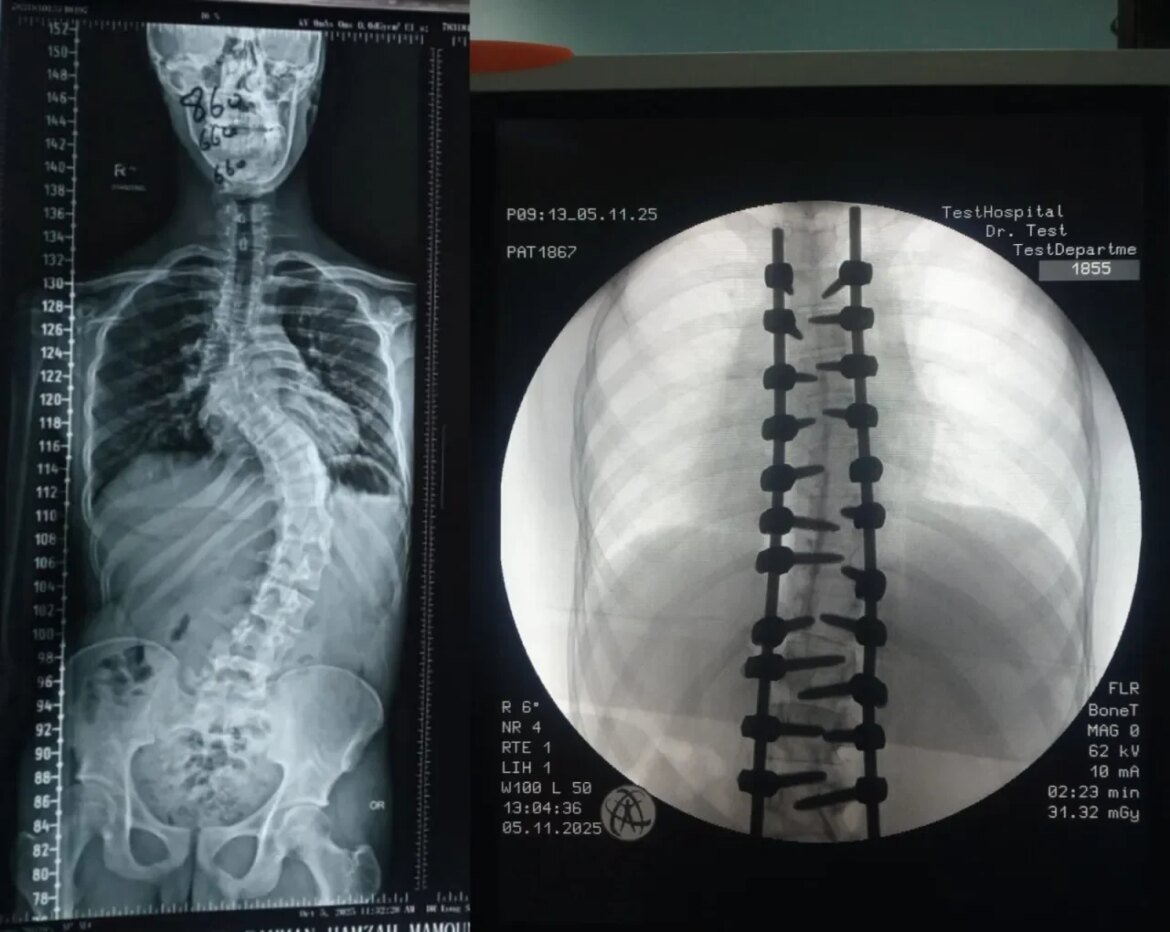

شهد قسم جراحة العمود الفقري في مستشفى الأمير حمزة إنجازًا طبيًا مميزًا تمثّل في إجراء تدخّل جراحي معقّد لتصحيح جنف العمود الفقري لدى أحد المرضى الذين يعانون من تشوّه حاد في الفقرات.

وقد أُجريت العملية باستخدام جهاز الملاحة الجراحية المتقدّم، الذي أتاح دقةً عالية في التعامل مع التشوّهات البنيوية الشديدة، وسهّل توجيه الأدوات الجراحية ضمن المسار الآمن والمثالي.

كما اشتملت العملية على إزالة أجزاء محددة من الأطراف الخلفية للفقرات لتحقيق التصحيح المطلوب واستعادة التوازن والمحاذاة الطبيعية للعمود الفقري.

وتم تنفيذ هذا الإجراء الدقيق تحت نظام مراقبة الأعصاب المتواصل (Intraoperative Neuromonitoring) لضمان سلامة الوظائف العصبية طوال مراحل العملية.

وقد نُفّذ هذا التدخل الجراحي بقيادة الدكتور إبراهيم القاسم، أخصائي جراحة العمود الفقري والتشوّهات الخَلقية، والدكتور محمد الطراونة، رئيس قسم جراحة الأعصاب، وبمشاركة كلٍّ من المقيمين: د. محمد محمود نعمان (مقيم جراحة الدماغ والأعصاب)، ود. أحمد الرواشدة (مقيم جراحة العظام)، إضافةً إلى فريق التخدير برئاسة الدكتور راسم عبدالرزاق